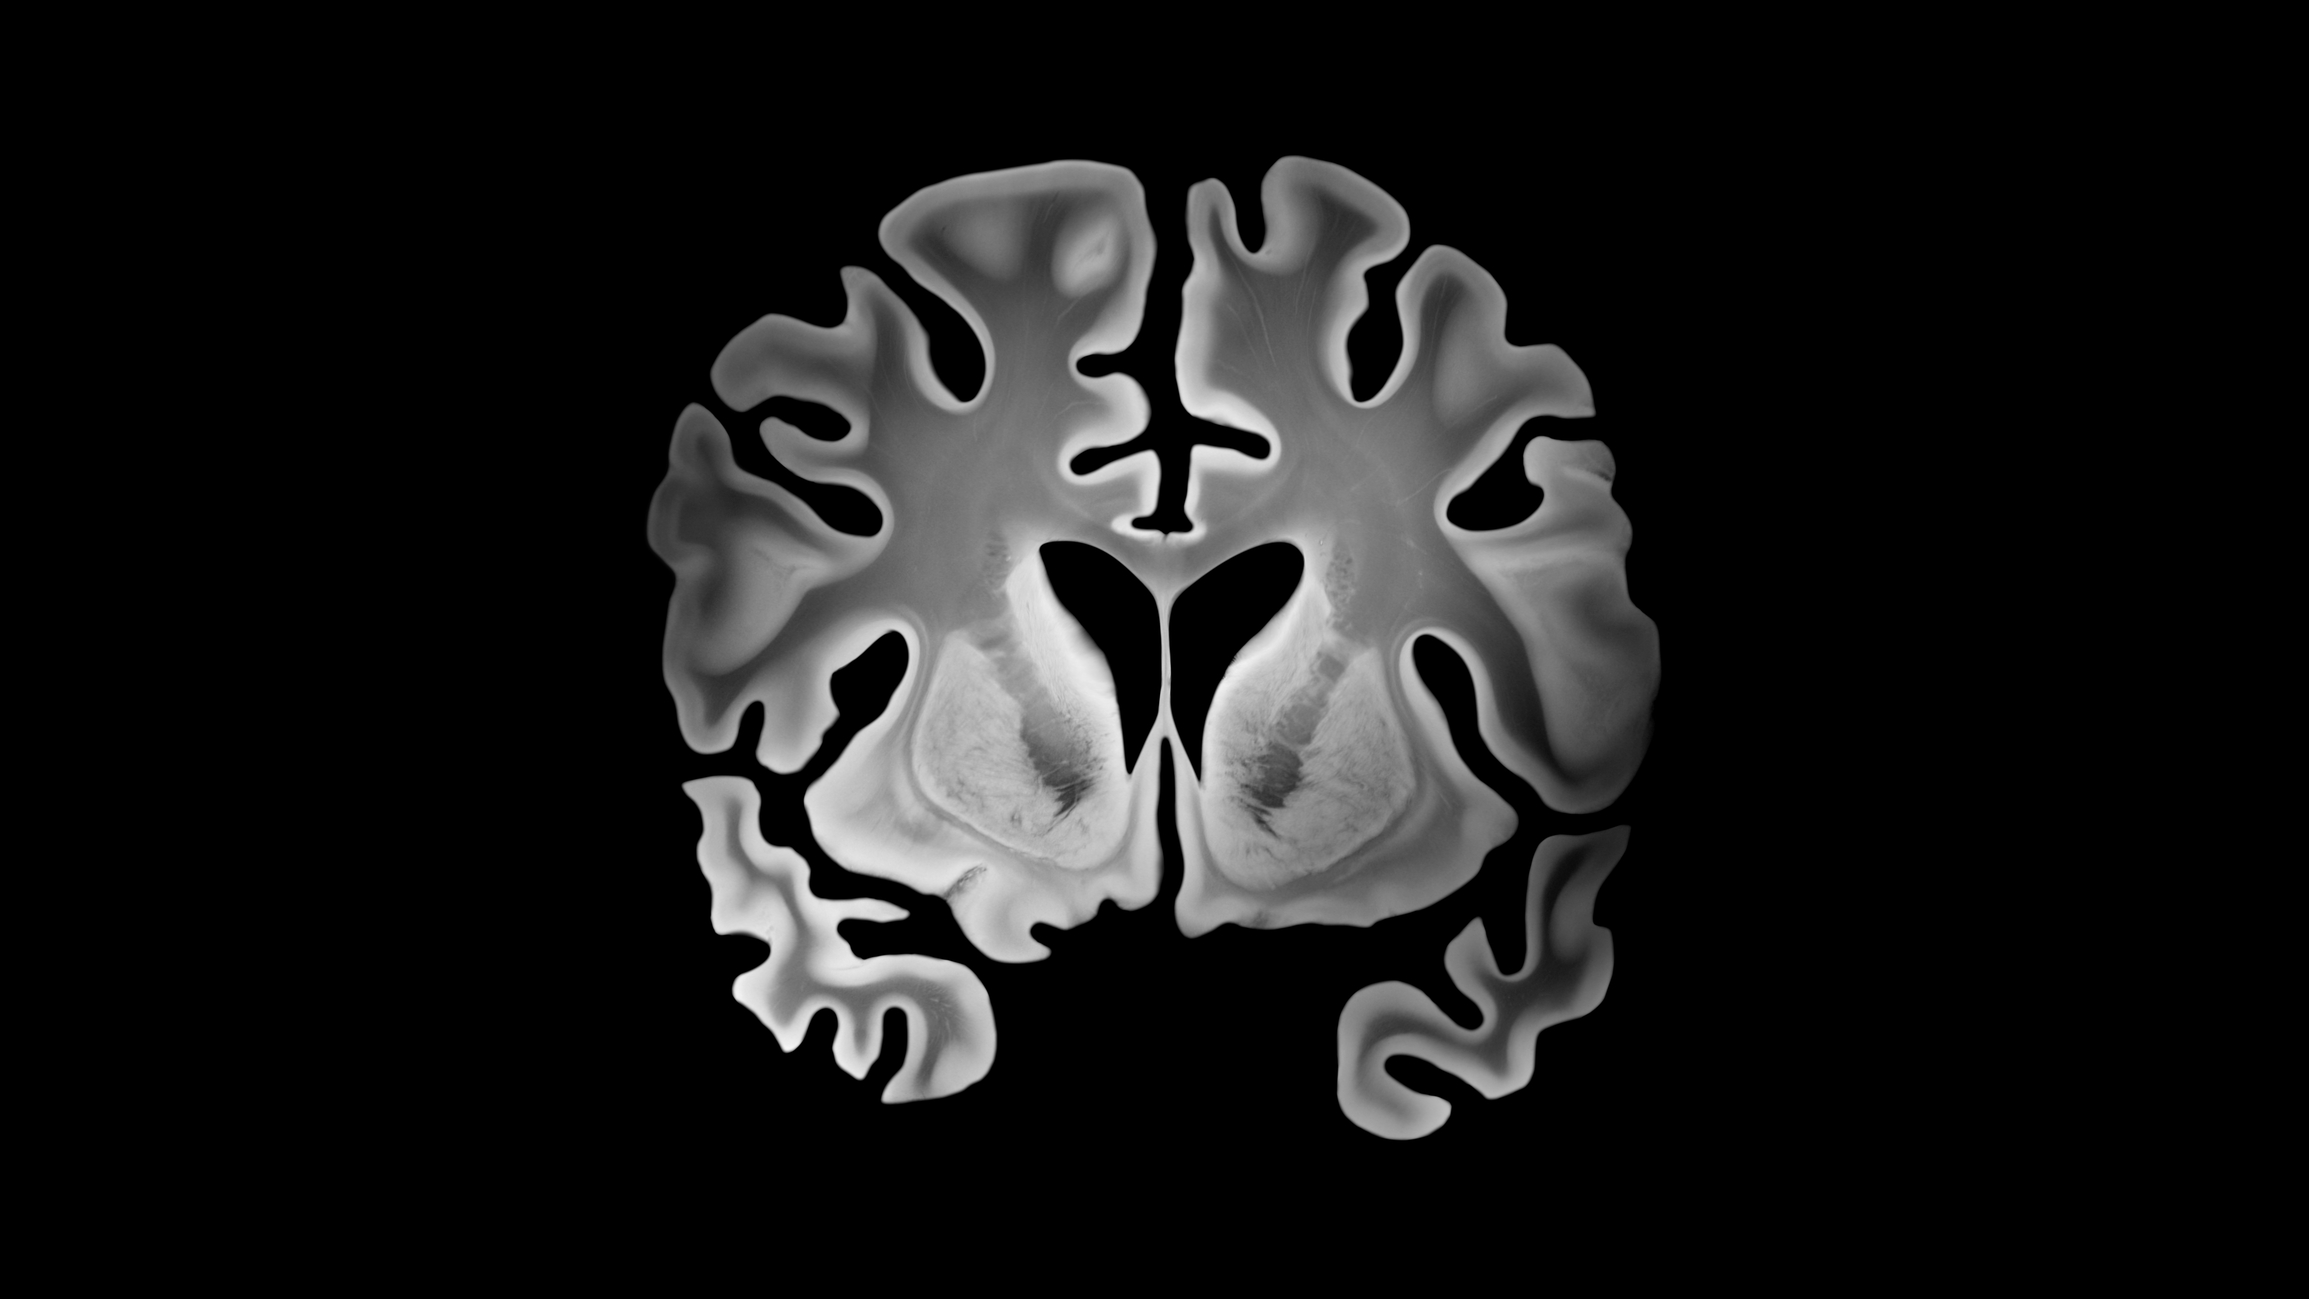

La acumulación de proteínas anómalas, como la beta amiloide y la tau fosforilada, es una de las características centrales del Alzheimer. Con el tiempo, estas proteínas se agrupan formando placas y ovillos que interrumpen la comunicación entre las neuronas y dañan el tejido cerebral.

Los científicos descubrieron que una molécula producida de manera natural en el organismo podría ayudar a descomponer y eliminar estas proteínas tóxicas antes de que formen depósitos peligrosos. Las pruebas de laboratorio demostraron que esta molécula actúa como un “limpiador biológico”, capaz de activar procesos celulares que degradan proteínas defectuosas.